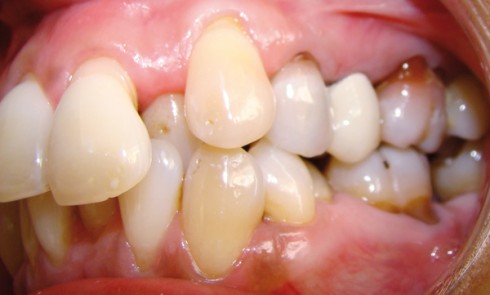

La patiente est une adulte de 22 ans présentant une rétrognathie mandibulaire associée à une endoalvéolie mandibulaire avec un défaut...